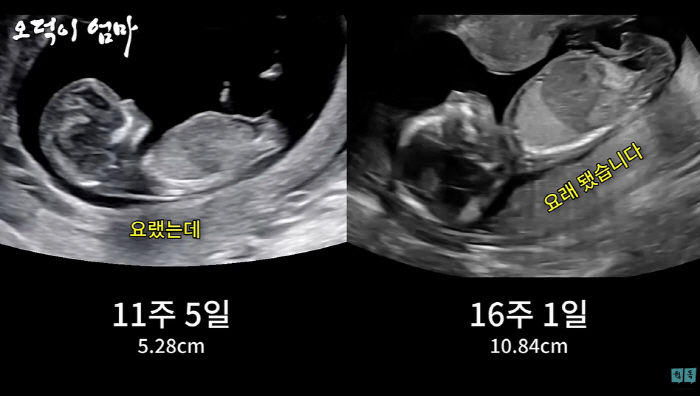

한달 사이에 2배 성장한 아이는 벌써 11cm정도로 자랐다. 황보라는 "신기하네 어떻게 저렇게 조그만 몸 안에 척추가 다 있지"라며 팔을 구부려서 목 뒤로 넘기고 있다는 말에 "우리 신랑이 좋아하는 자세"라고 웃었다.

그때 황보라 눈에 들어온 한 부분. 황보라는 "고추다. 아들이다. 누가 봐도 어들이다"라며 설레발 쳤다. 의사 선생님은 32주 전에 성별을 알려줄수 없는 법 때문에 침묵을 지켰다.